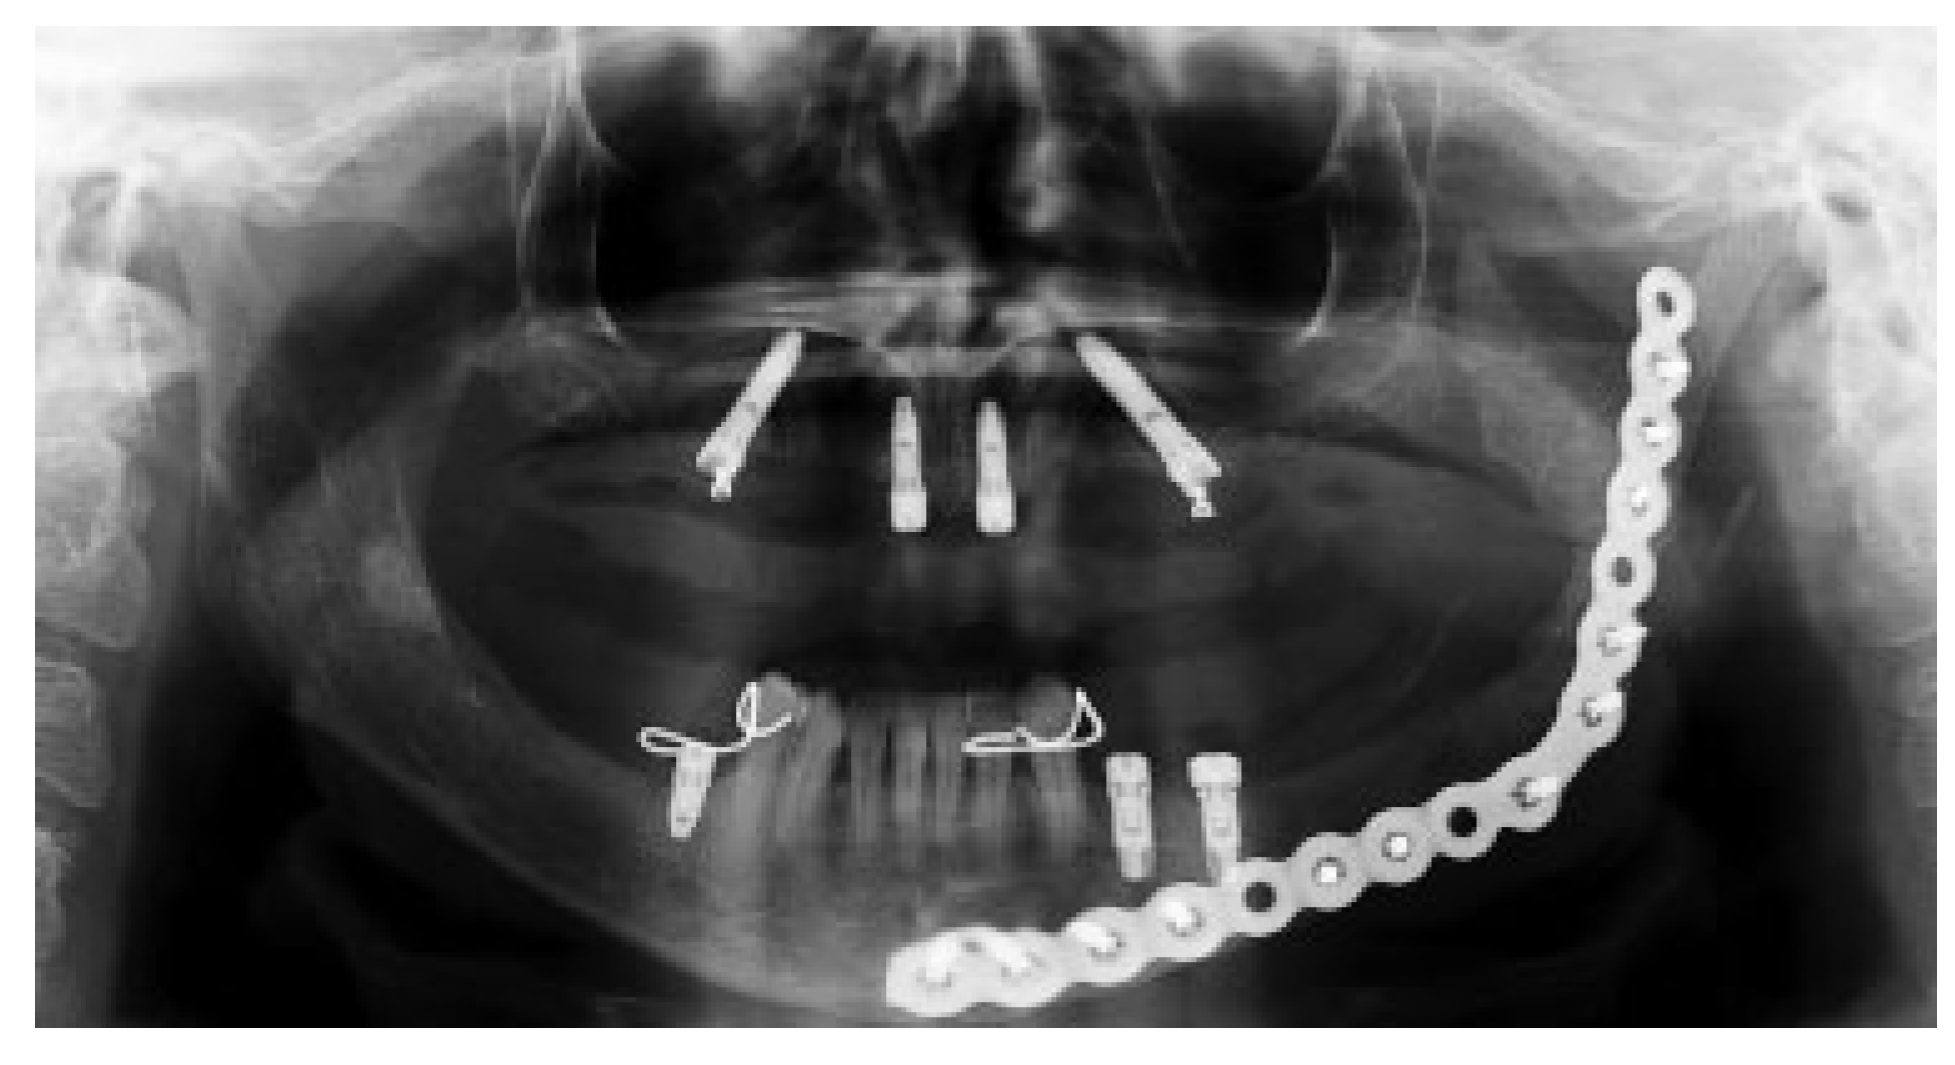

Figure 1. Radiographic examination showing the lesion in the left body mandible.

Figure 4. (a) Panoramic radiographic demonstrating the resected area and the 2.4 mm reconstruction plate placed from the left mandibular ramus to the parasymphysis. (b) Sagittal CT scan demonstrating the resected area and the 2.4 mm reconstruction plate placed from the left mandibular ramus to the parasymphysis. (c) 3D-reconstruction CT scan demonstrating the resected area and the 2.4 mm reconstruction plate placed from the left mandibular ramus to the parasymphysis. CT, computed tomography; 3D, three dimensional.

Figure 8. Panoramic radiograph showing the implants placed in the maxilla and mandible, with no evidence of tumor recurrence after 3 years of surgical resection.

A 46-year-old Caucasian female presented to the Oral Surgery Department at Alameda County Medical Center–Highland General Hospital, complaining of dental pain in maxillary left region for 2 months. Her medical history was significant for hypertension and congestive heart insufficiency for which she takes enalapril, carvedilol, furosemide, and Klor-Con (Klor- Con®, Upsher-Smith Laboratories, Inc., Morristown, NJ) (potassium chloride). She is allergic to codeine. She has a 10 pack- year history of smoking and a remote history of methamphetamine use. Her past surgical history is significant for parathyroid carcinoma, which resulted in primary HTP. She reported that time weight loss, hives, insomnia, fatigue, and bone pain before surgical excision performed 17 years ago. No uterine or kidney lesions were present. She also reported that her brother had a jaw tumor, not surgically treated, because the “jaw growth stopped.” Unfortunately, her brother does not live in the city, and a better investigation concerning his disease could not be performed. Extraoral examination revealed a small swelling in the left mandibular border. Intraorally, the patient presented with poor hygiene with multiple extensive dental caries and periodontal disease. An asymptomatic and firm posterior left mandibular swelling was also present, with buccal and lingual expansion. Radiographic and computed tomography (CT) scan examination revealed a 5-cm mixed radiolucent and radiopaque image in the left mandibular body with well-defined borders and base expansion (Figure 1 and Figure 2a,b). An incisional biopsy was obtained with an intraoral approach which was diagnosed as a benign fibro-osseous lesion, consistent with ossifying fibroma. Initial laboratory analysis prior surgery showed a small increase in serum calcium of 10.5 mg/dL (8.4–10.2 mg/dL). Based on these findings and with the history of parathyroid carcinoma, the patient was referred to an endocrinologist. CT scan of the neck was unequivocal for recurrence and no correction of serum calcium was necessary. The association of ossifying fibroma with primary HPT due parathyroid carcinoma, with a family history of a similar jaw lesion, led to a high suspicion of HPT-JT syndrome. It was extensively discussed with the patient, but she refused to perform any genetic test. Our treatment planning initially included the extraction of the left inferior premolars, which had extensive caries lesions and mobility, performed before the lesion surgical removal. It would enable a better wound closure after resection. Three months later (2010 March), the ossifying fibroma was surgically resected with 5 mm margins (Figure 3) using an intraoral approach, and a 2.4-mm reconstruction plate was placed from the left mandibular ramus to the parasymphysis (Figure 4a–c). The postoperative course was remarkable only for neurosensory disturbance in the left inferior alveolar nerve, which improved but was not completely resolved after 3 years of follow-up. Seven months later (2010 October), using an extraoral approach, the patient underwent a left mandibular reconstruction using her left posterior iliac crest, as well as the right anterior iliac crest. The corticocancellous blocks were secured with 2.4 mm monocortical screws, while cancellous bone chips were inserted between the block grafts (Figure 5a–c). Although regular follow-ups were performed within the first 4 postoperative months, the patient recently returned to the oral surgery clinic for revaluation in 2012. Clinical and radiological examinations (Figure 6) were performed, and oral rehabilitation with dental implants was planned (June 2012). The patient subsequently underwent a third surgical intervention, under local anesthetic and intravenous sedation. The remaining maxillary teeth were extracted, followed by osteoplasty and placement of four implants: two anterior axially placed and two posterior tilted placed. At the same operating time, monocortical screws were from the mandible and three implants were placed in the region of teeth 20, 21, and 28, and alloplastic bone graft was placed covering the exposed threads of the implants (Figure 7a,b). A temporary superior and inferior prostheses were subsequently placed, and a period of 6 months for implant osseointegration before final prosthesis rehabilitation is being observed. The patient is currently followed regularly and, after 3 years of surgical resection, no evidenceof tumor recurrence is seen (Figure 8). Therefore, no evidence of parathyroid carcinoma recurrence is seen after 21 years of endocrinological follow-up.